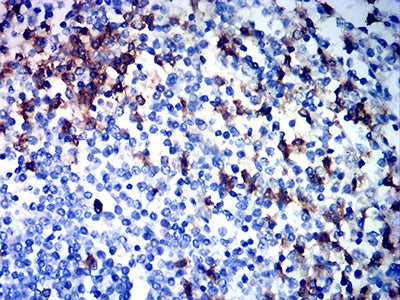

分类: 科研抗体货号: 32189别名: CR3A; MO1A; CD11B; MAC-1; MAC1A; SLEB6应用: IHC,FCM反应种属: Human